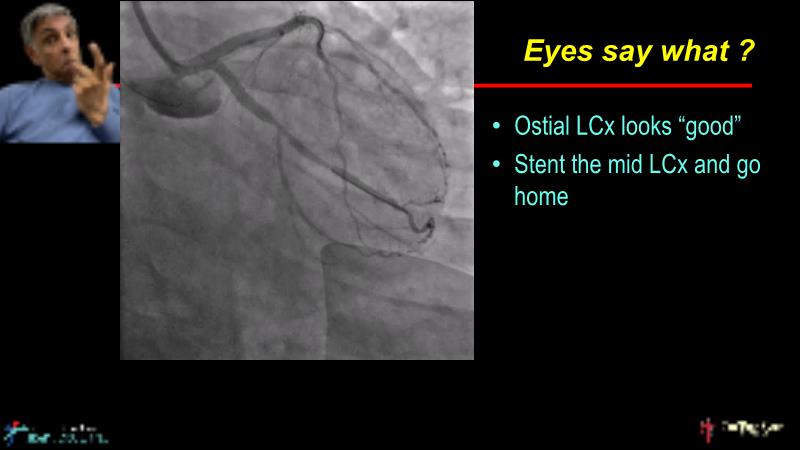

This session is recommended for you if you are seeking insights into the advantages of using IVUS imaging over visual assessment for better outcomes in left main bifurcation procedures. Discuss with experts the benefits of using RotaCUT in lesion preparation for left main bifurcation and explore the impact of high radial strength stents on the procedure's success.

• To understand why the use of IVUS imaging is different from seeing with experienced eyes to achieve improved left main bifurcation outcome